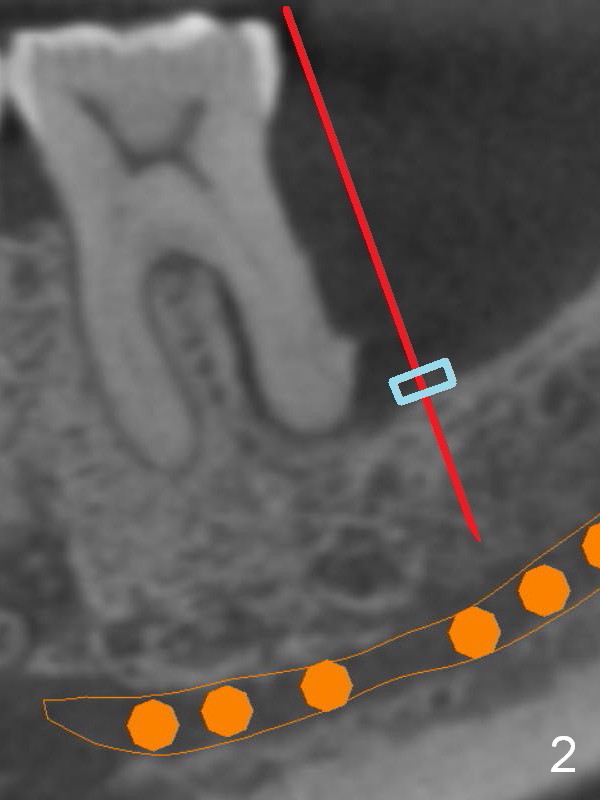

There is severe bone resorption around the distal root of the lower left 1st molar of the 56-year-old man (WG), while the loss of the 2nd molar is associated with limited bone height (Fig.1). A 5x14 mm implant will be placed at the mesial socket of #19 and 5.9 or 6.4x6 mm one is at the mesial site of #18 (Fig.7-9). Use a 2 mm pilot drill with 6 mm stopper from Sinus Master Kit (with extension) to initiate osteotomy at #18 immediately distal to the crown of #19, parallel to the long axis of the latter (Fig.2). After inserting a parallel pin at #18, extract the tooth #19 (Fig.3, antibiotic pending) and start osteotomy with a 2 mm pilot drill with 14 mm stopper (Fig.4). Insert the calibrated parallel pin at #19 (Fig.5) and measure the distance between the two parallel pins (approximately 10 mm, Fig.7). Sequential osteotomy and application of the Tatum taps (Fig.6 red rectangle) will push the septum distal (green arrow). As to #18 osteotomy, trephine, final and tap drills are to be used with control of the depth: 6 mm (Fig.7,9).